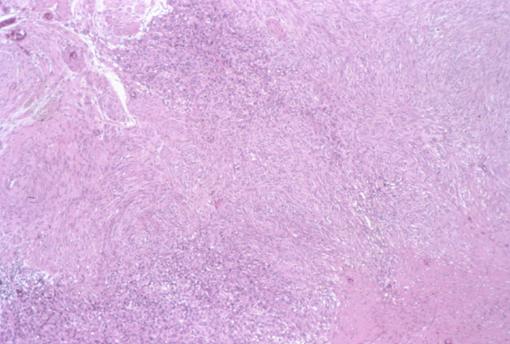

악성 비상피성 평활근육종(위)

3년 3개월간에 약 2.5배 증대한 위의 평활근육종

악성 비상피성종양/평활근육종

위(부위)/체부

마이크로

1형(종괴형)/

20~24

mp